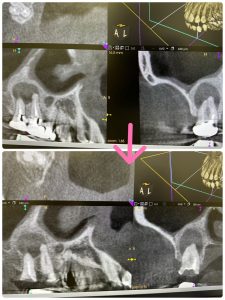

ヤグレーザー各根1分❌6根

意図的に穿通させてるから、ヤグレーザーの殺菌は抜群、更には特効薬カルビタール貼薬1カ月に1回

漏洩リケージ防止に仮歯装着

6根から病巣を狙い撃ち🤪

前歯単根より、治りは早いと思う